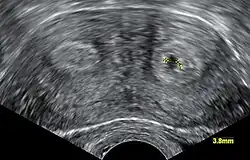

Diagnose

Die medizinische Diagnose wird in der Regel durch Sonografie gestellt.